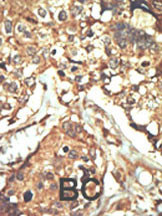

Formalin-fixed and paraffin-embedded human cancer tissue reacted with the primary antibody, which was peroxidase-conjugated to the secondary antibody, followed by AEC staining. This data demonstrates the use of this antibody for immunohistochemistry; clinical relevance has not been evaluated. BC = breast carcinoma; HC = hepatocarcinoma. |